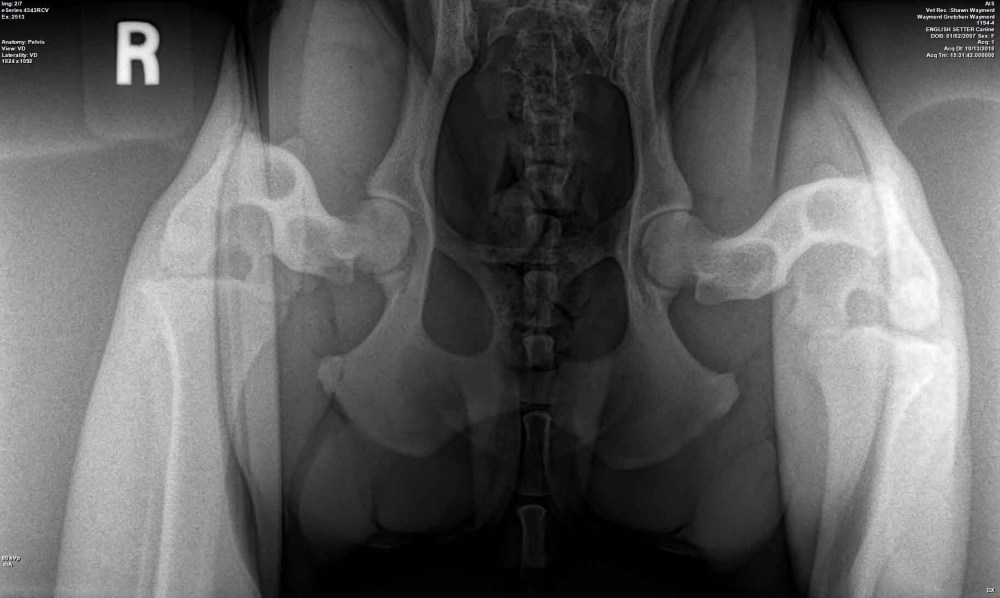

Ron Boehme, the host of the awesome Hunting Dog Podcast, asked if I ‘d contribute some veterinary specific advice to his Blog on the Hunting Dog Podcast…which I gladly accepted the challenge. Here’s the link to my latest contribution http://thehuntingdogpodcast.com/2017/04/canine-hip-dysplasia-and-pennhip/.